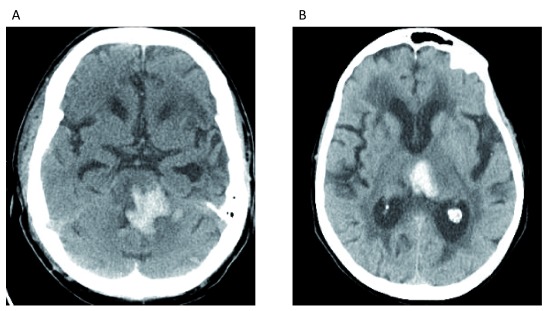

Figura 1.Figura 1. Emorragia intracerebrale dovuta a ipertensione arteriosa.(A) Emorragia iperattenuante visualizzato nel pons. (B) Emorragia iperattenuante iperattenuante centrata nel talamo mediale sinistro. Entrambe le posizioni sono tipiche per l’emorragia legata a lungo termine arteriopatia ipertensiva. Queste immagini costituiscono dati originali e inediti ottenuti dagli autori.

Fattori di rischio modificabili per ICH includono l’ipertensione arteriosa (Figura 1), il consumo eccessivo di alcol, la diminuzione del colesterolo lipoproteico a bassa densità, i bassi livelli sierici di trigliceridi, i farmaci su prescrizione, il fumo di sigaretta corrente, e le droghe di abuso (per esempio, cocaina, eroina, anfetamine ed efedrina)1. L’ipertensione arteriosa è uno dei più importanti fattori di rischio modificabili in quanto la prevalenza grezza tra gli adulti negli Stati Uniti è stata stimata al 45,6%; si tratta di un aumento dal 31,9% in base alle precedenti definizioni di ipertensione arteriosa2. Alcuni farmaci su prescrizione, come gli inibitori della cicloossigenasi (COX), gli inibitori della P2Y12, gli OAC, gli inibitori selettivi della ricaptazione della serotonina (SSRI) e le statine, sono stati associati ad un aumento del rischio di ICH.